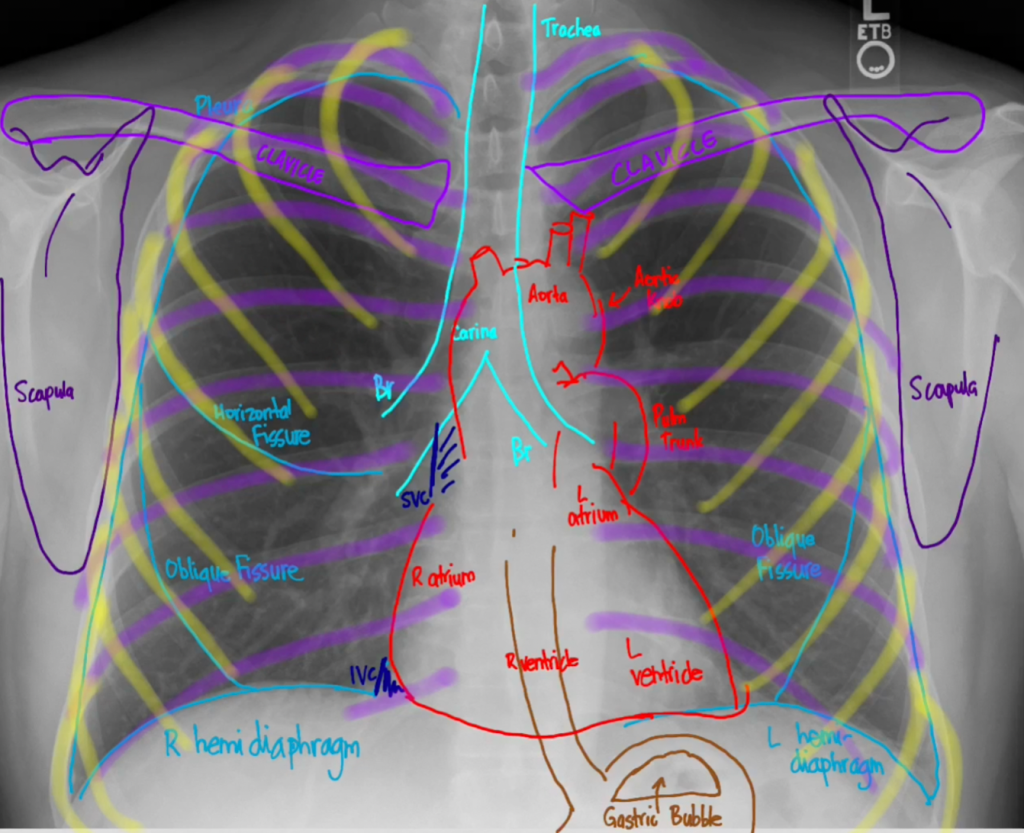

Anatomy of the Chest X-ray

Before we dig into an approach for reading chest x-rays, it’s important to know all the things that we’ll looking at. There are typically two views you’ll be looking at PA and lateral. The PA or posterior to anterior shoots a beam from a standing patient’s back through to their front, where the x-ray plate collects it. The lateral shoots the beam through the standing patient’s size through to the other side where the x-ray plate collects it.

| Soft Tissue and Bones | Look for any lesions in the bones. Look at the vessels (like the aorta). Look at the soft tissues, is there any air (black)? |

| Airways and Mediastinum | The carina and trachea should be in the midline. And the mediastinum should be less than 8 cm in width. |

| Breathing | Look at the vascularity. They should start to disappear at the periphery, but you can usually still see a few. If it’s all black, consider a pneumothorax. Look for infiltrates and fluids in the fissures and the costophrenic angles. |

| Circulation | Look at the heart, ⅔ will be on the left side. The cardiothroacic ratio should be about half the distance of the thorax. Heart should have a non-boot shape and be distinct. |

| Diaphragm | Right hemidiaphragm is usually higher than the left There should be no air underneath but you will see the gastric bubble on the left side. |